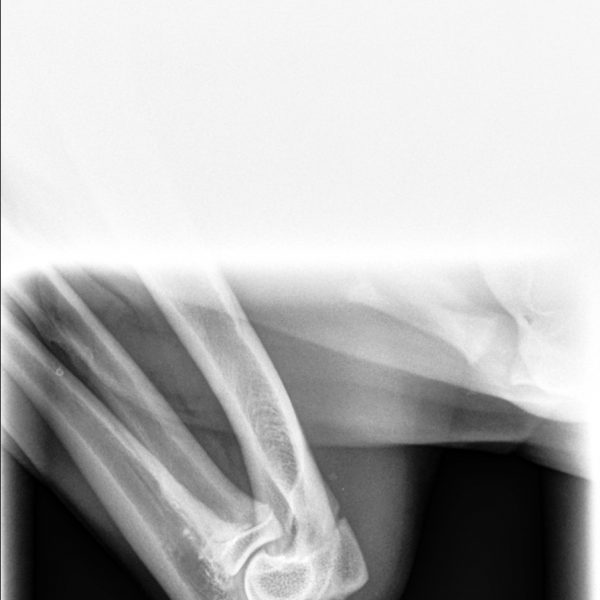

- MDBA Australian Cobberdog breeding female.

Arrowhead Adsila